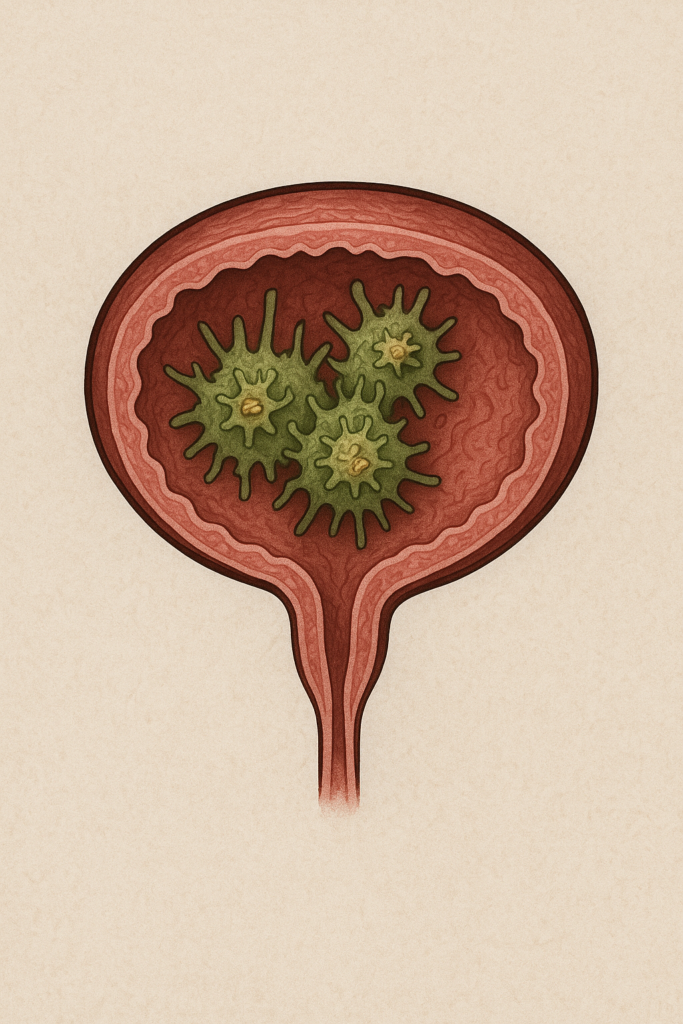

STAGE 1 – CHAOS

Harmful bacteria dominate your urinary tract. Your bladder is under constant attack: chronic inflammation, false urgency signals, involuntary contractions. Leaks when coughing, laughing, sneezing become daily torture.